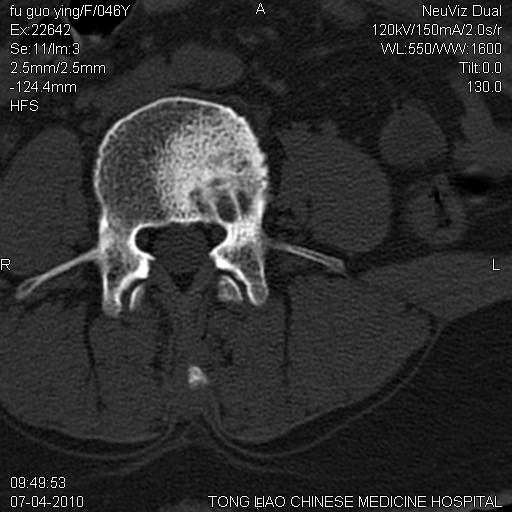

标题: CT27489:患者腰疼,其余椎体未见异常! [打印本页]

标题: CT27489:患者腰疼,其余椎体未见异常!

女性46岁,左髂骨溶骨性破坏+软组织肿块,考虑转移瘤,腰椎为退变/增生硬化/软骨下骨囊变。

髂骨考虑转移瘤 椎体病变不像转移瘤